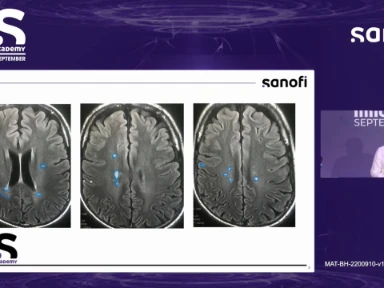

The Underlying Biology of Neuroinflammation

Leading experts, Dr. Alexandre Prat and Dr. Heinz Wiendl discussing the underlying biology of neuroinflammation.